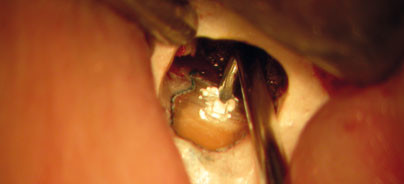

Das Freilegen der Wurzelspitze wird rotierend mithilfe von Kugelfräsen eines Durchmessers von 2mm und kleiner durchgeführt. Die Resektion sollte mittels eines leicht konischen Bohrers erfolgen und umfasst drei Millimeter der Wurzelspitze in einem Winkel von nahezu 90 Grad zur Zahnachse (Abb. 5). Dies eliminiert 93 Prozent aller lateralen Kanäle und 98 Prozent aller Ramifikationen (Kim 2001). Anschließend erfolgt die Kürettage des pathologischen apikalen Gewebes, gefolgt von einer suffizienten Blutstillung. Mithilfe von Eisen-III-Sulfat (Astringedent, Fa. Ultradent) getränkten sterilen Pellets wird ein Gefäßverschluss innerhalb der knöchernen Kavität durch Oxidation des Blutes und Agglutination der Blutproteine herbeigeführt. Danach wird der  Vitalfarbstoff Methylenblau appliziert, der selektiv das Weichgewebe (PA-Spalt, Endodont, Isthmen) und feine Mikrorisse anfärbt. Bei der Inspektion des Neoapex ist ggf. mithilfe von Mikrospiegeln das Vorliegen von nicht abgefüll-ten Kanälen, Isthmen, Wurzelfrakturen sowie inkompletten Wurzelresektionen zu überprüfen. Von Arx und Mitarbeiter konnten 2011 zeigen, dass 83 Prozent aller resezierten Zähne Undichtigkeiten der WF am Neoapex aufweisen. Dies unterstreicht die Forderung eines erforderlichen neuen retrograden Verschlusses des Wurzelkanalsystems nach Ultraschallpräparation aller identifizierten Wurzelkanäle und Isthmen. Die zusätzliche retrograde Ultraschallaufbereitung verbessert die Prognose der WSR um 17 bis 30 Prozent (Kim & Kratchmann, 2006). Diese erfolgt 3mm tief, kanalachsengerecht mit abgewinkelten diamantierten Spitzen (Abb. 6). Besitzen die behandelten Wurzeln mehr als zwei Kanäle ist unter Variation der mikroskopischen Perspektiven auf die Inzidenz von Isthmen zu achten, die von Cambruzzi und Marshall im Jahre 1983 erstmals beschrieben wurden. Die Isthmus-Inzidenz variiert je nach Zahn und Resektionshöhe und ist in der mesialen Wurzel des ersten Unterkiefermolaren mit 80 Prozent am höchsten. Die Abbildung 7 zeigt den Zustand nach retrograder Isthmus- und Kanalaufbereitung.